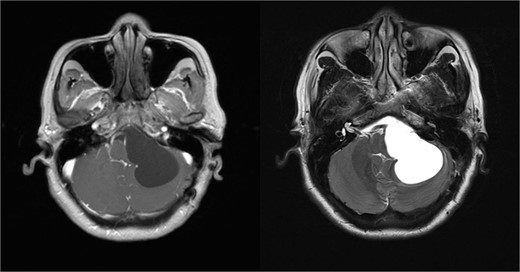

We found the patient with a visual analog scale of 8/10 on the physical examination. The Romberg test was positive on the left side, while other neurological examinations were within normal limits. A magnetic resonance imaging (MRI) of the head revealed an extra-axial cystic lesion in the left cerebellopontine angle (Fig. 1), compressing the left cerebellar hemisphere posteriorly, displacing the pons to the right, narrowing and displacing the fourth ventricle to the right, causing non-communicating hydrocephalus. We then planned surgery with a retrosigmoid approach to remove the cyst wall and decompress the brainstem.

MRI examination reveals an extra-axial cystic lesion appearing dark on T1-weighted images and bright on T2-weighted images.

Radiologically, neurenteric cysts typically appear as extra-axial masses on the midline of the posterior fossa. Computed tomography (CT) scans usually show hypodense lesions. On MRI, signal intensity depends on the protein content of the cyst fluid. In cases with high protein content, the cysts appear isointense or slightly hyperintense on T1-weighted images compared to cerebrospinal fluid and are usually very hyperintense on T2-weighted images [1, 5, 8]. Neurenteric lobulated cysts do not enhance with contrast, mostly ˂2 cm without calcification. Hydrocephalus may occur if the cyst obstructs the cerebrospinal fluid outflow on the fourth ventricle level. Due to nonspecific radiological features, the differential diagnosis for neurenteric cysts is very wide, including arachnoid cysts, choroid plexus cysts, colloid cysts, dermoid cysts, epidermoid cysts, primary or metastatic cystic tumors, and Rathke's cleft cysts [1, 9]. In our case, the lesion was suspected to be an arachnoid cyst due to its similar radiological appearance and location in the cerebellopontine angle (CPA) region.